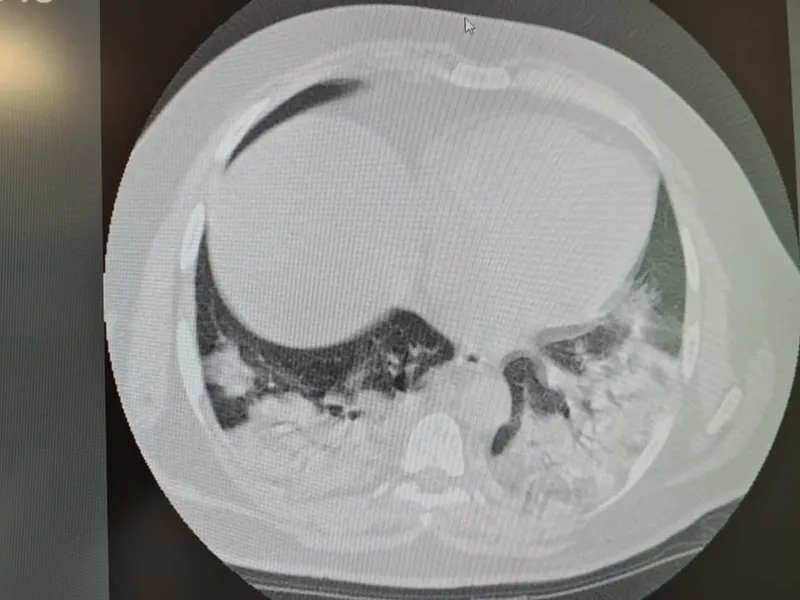

FOTO Cum arată plămânii unui tânăr cu COVID, în stare gravă la spital, după tratament cu ivermectină

Dr. Elena Copaciu, medic primar ATI, a publicat, pe pagina sa de Facebook, imagini cu plămânii unui tânăr care s-a tratat cu ivermectină (medicament de uz veterinar).

„Știu din experiența de zeci de ani de terapie intensivă că oamenii vor să primească vești pozitive! Le este sete de vești bune! Chiar și atunci când veștile nu pot fi bune! In pandemie, mai mult decât oricând are loc această distorsiune! Un exemplu: pacient tânăr tratat cu ivermectină de uz veterinar până când necesarul de oxigen a impus internarea in spital( de uz uman!)...doar că: prezentare tardivă, multă fibroză pulmonară și tendință la micro abcedare (abces pulmona, n.r.) în unele zone! ...”, a atras atenția medicul ATI Elena Copaciu, pe Facebook.

Fibroza pulmonară determină apariția sindromului de insuficiență respiratorie, iar abcesul pulmonar (numit și pneumonie necrozantă sau gangrenă pulmonară) formează în plămâni cavități necrozante sau fluide, conform RoMedic.ro.

Sursă imagine: Facebook Dr. Elena Copaciu